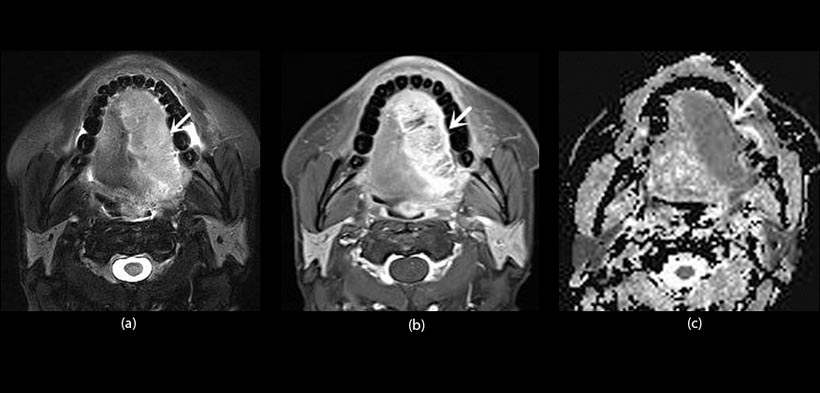

Fig. 1. Paciente varón de 55 años de edad con diagnóstico de carcinoma de células escamosas. (a) vista axial T2, imagen ponderada con supresión de grasa muestra una masa homogénea hiperintensa (flecha) en la parte lateral derecha de la lengua, que se extiende a través de la línea media, (b) Imagen con mayor contraste, vista axial de RM ponderada en T1 con supresión grasa demuestra realce heterogéneo (flecha). (c) coeficiente de difusión aparente (ADC), revela una masa hipointensa (flecha). El valor ADC es 1.17x103mm2s-1.